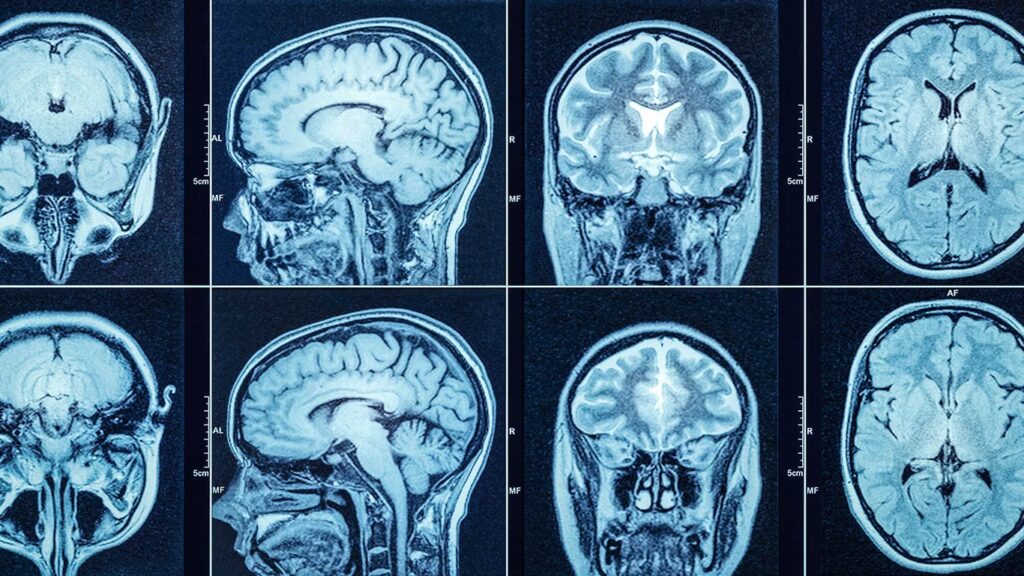

La tomografía computarizada de cabeza, comúnmente conocida como TAC o escáner CAT, es una técnica de imagen médica de diagnóstico fundamental en la evaluación de diversas afecciones cerebrales y craneales. Utiliza equipos de rayos X especializados para generar imágenes detalladas del interior de la cabeza, proporcionando información invaluable para los médicos.

A diferencia de las radiografías tradicionales, que producen una única imagen bidimensional, la TAC de cabeza toma múltiples imágenes desde diferentes ángulos. Una computadora procesa estos datos para crear 'cortes' transversales detallados del cuerpo. Estas imágenes pueden luego ser reformateadas en múltiples planos, e incluso generar imágenes tridimensionales, ofreciendo una vista mucho más completa y detallada de órganos internos, huesos, tejidos blandos y vasos sanguíneos. Esta capacidad de detalle es particularmente crucial para estructuras como el cerebro.

Una computadora potente procesa este gran volumen de datos para crear imágenes transversales detalladas en dos dimensiones, como si se cortaran 'rebanadas' del cuerpo. Los escáneres de TAC modernos, conocidos como escáneres multicorte o multidetectores, pueden obtener múltiples cortes en una sola rotación, lo que resulta en imágenes más finas y detalladas en menos tiempo. Esta velocidad es particularmente beneficiosa para pacientes que tienen dificultad para quedarse quietos, como niños, ancianos o pacientes críticamente enfermos.